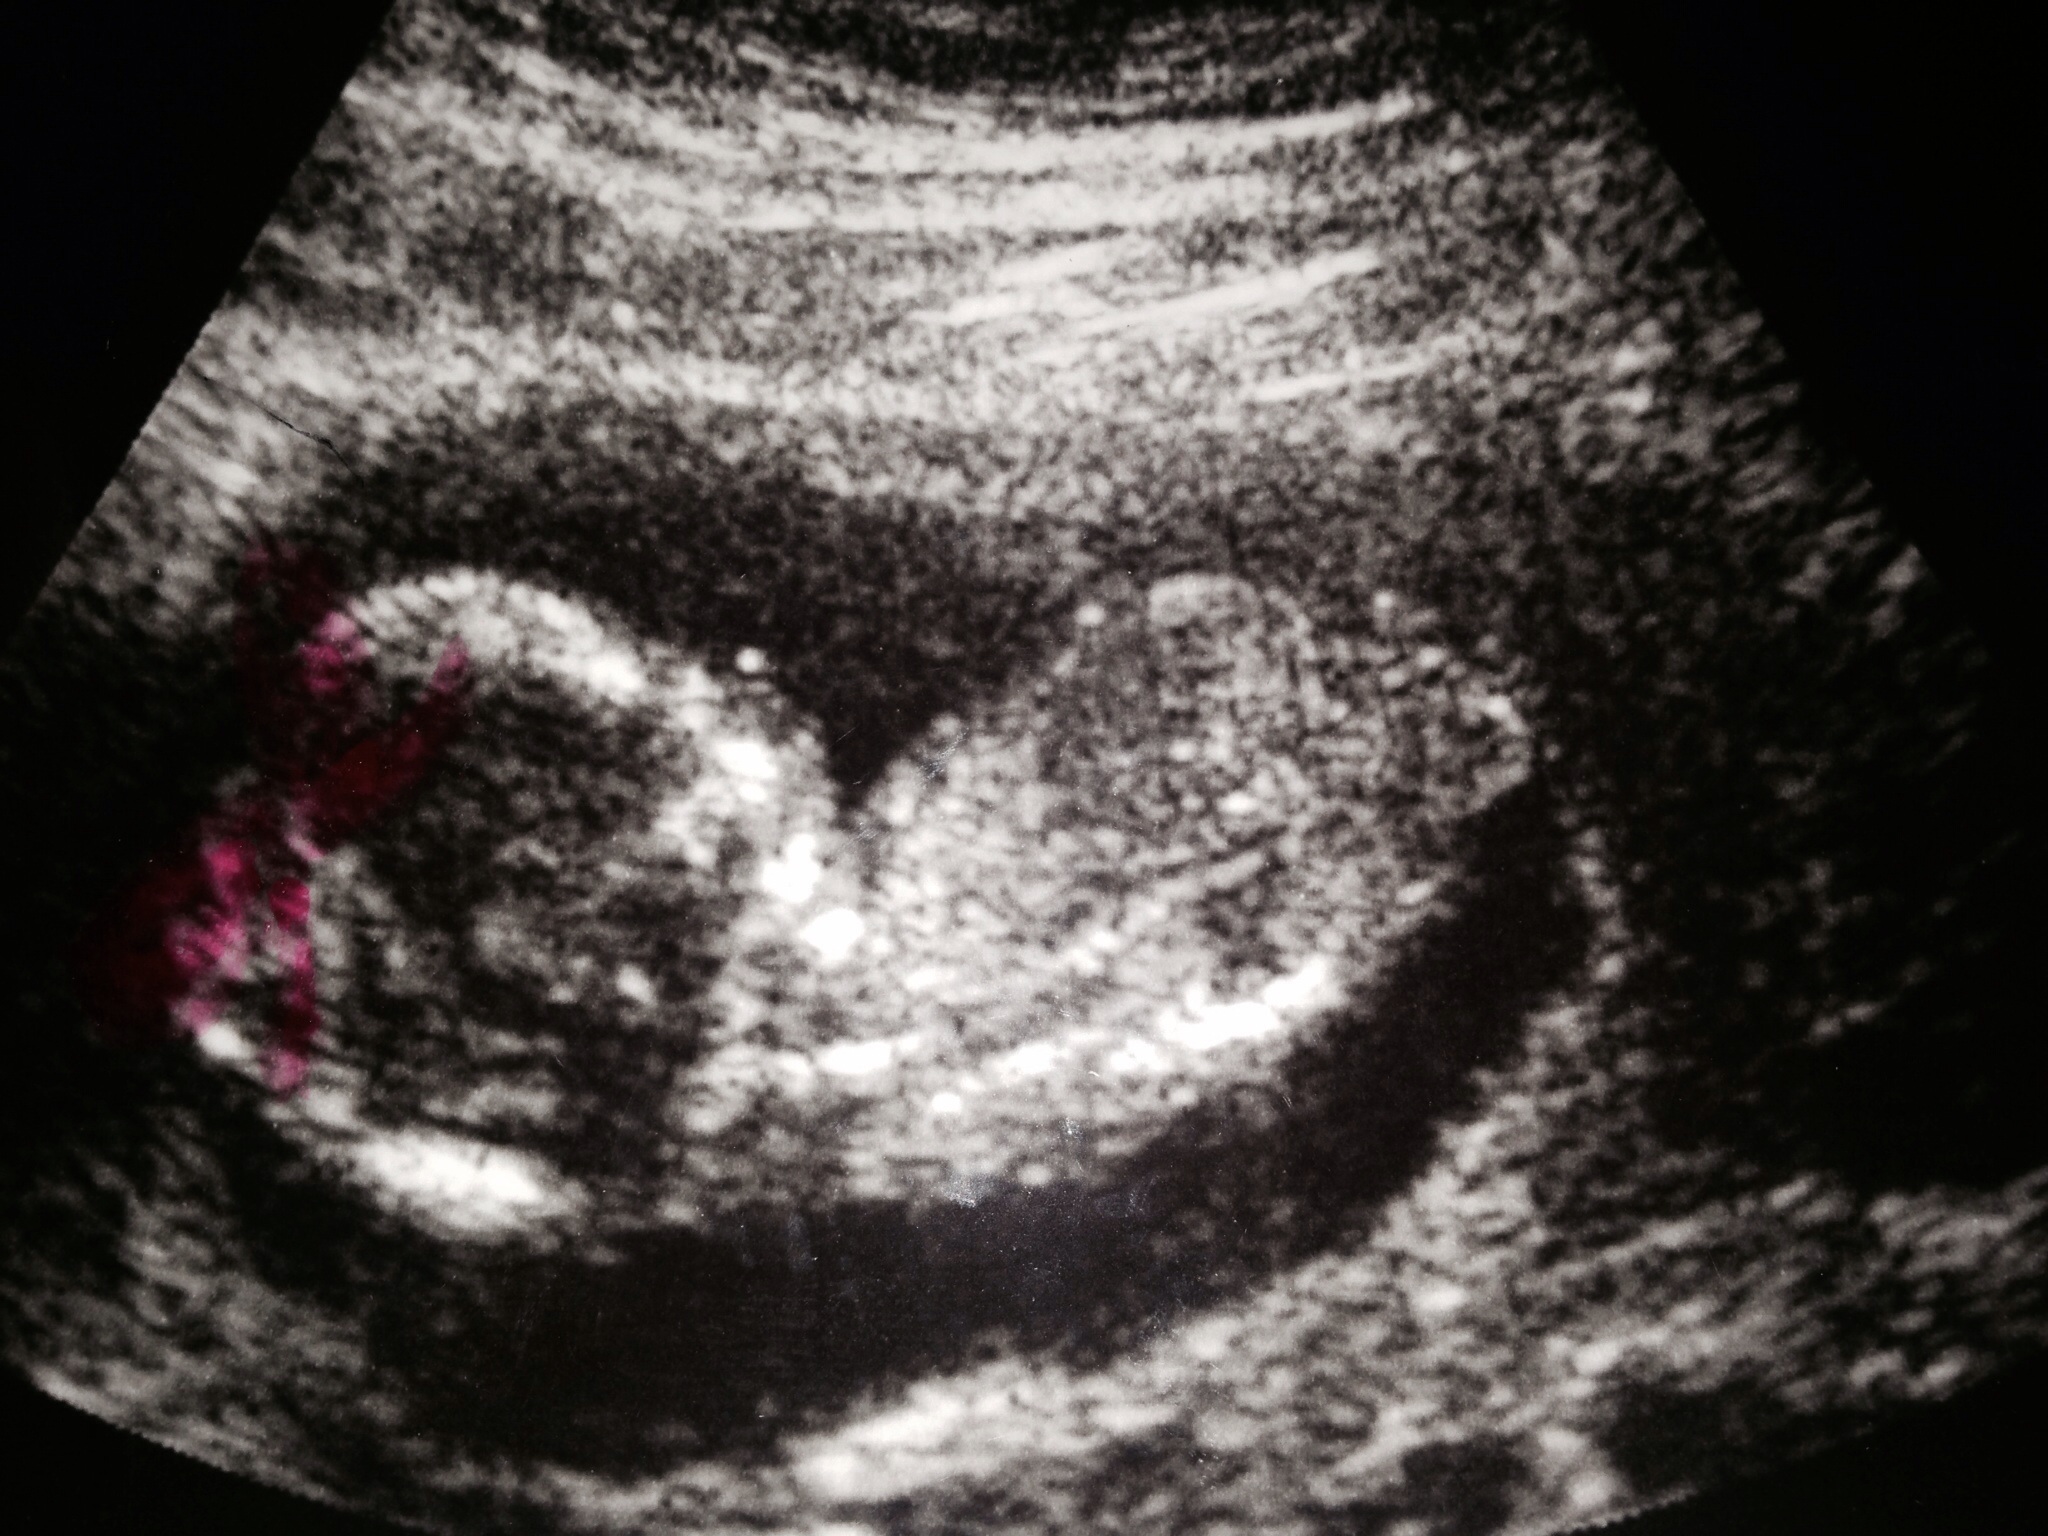

It's a GIRL and let me tell you, little missy didn't want to cooperate. She was too comfortable sleeping curled up against the placenta to show us her face or really anything other than her back. But she moved for a quick second and the ultrasound tech got a good shot. We're so excited!